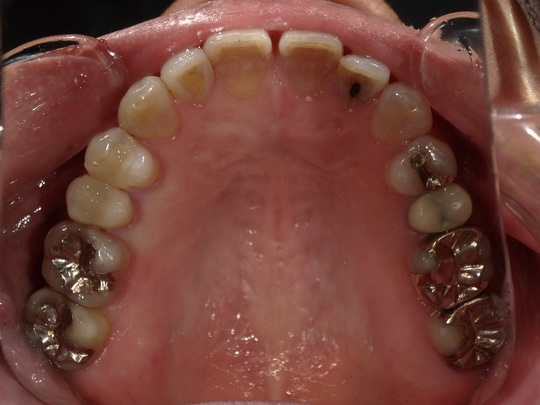

年齢:70代女性

治療内容:奥歯の銀歯が気になるという主訴で、右上中央から3,4,5番目をe.maxにより修復

治療期間/通院回数:3回

費用: e.max クラウン 110,000円x3本 ※2025年7月現在の価格